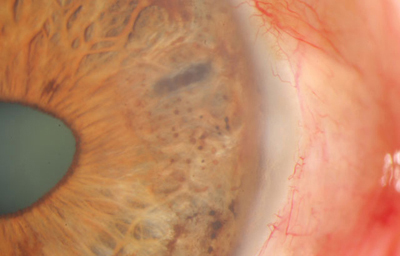

Colobomas típicos con diferentes grados de defecto en el desarrollo

Colobomas Atípicos.

Archivo Fotográfico Dr. Francisco Barraquer

Archivo Fotográfico Dr. Francisco Barraquer